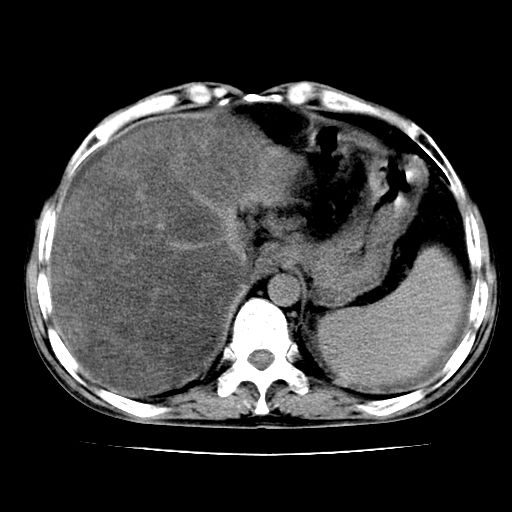

男,55岁,发现“肝硬化”5年,现腰疼、腹胀10余日,巩膜黄染、腹稍胀,肝肋下3指,质硬无压疼,移动性+,血生化:总胆、直胆、间胆均升高。

g1:肝硬化、脾大、腹水。

2:脂肪肝。

3:弥漫性肝癌待排。

肝硬化,脾大,腹水

脂肪肝

肝内多发低密度灶(建议增强扫描除外肝癌)

肝脾肿大,脂肪肝,腹水。建议增强除外肝癌。

肝占位待排

肝硬化,脂肪肝,腹水,肝癌